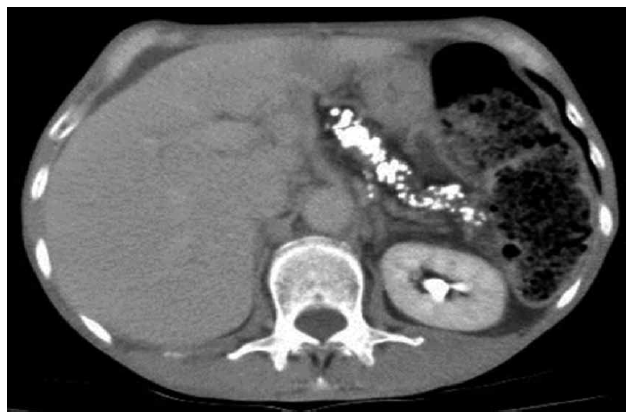

Hombre de 62 años con enolismo crónico y tabaquismo pesado activo. Refiere tres meses de deposiciones diarreicas amarillentas, flotantes, fétidas, doce diarias, que no mejoran con el ayuno, lo despiertan en la noche, con meteorismo, dolor abdominal, pérdida de 12/kg de peso y edemas periféricos. La tomografia de abdomen confirmó la sospecha de pancreatitis crónica e insuficiencia exocrina como causal de la diarrea crónica y esteatorrea 1. La pérdida de peso y malnutrición son hallazgos frecuentes de esta patología, se requiere suplencia con enzimas pancreáticas 2. El alcoholismo y el tabaquismo activo aceleran y contribuyen al progreso de calcificación 3,4 y en esta fase, hasta 90% de los pacientes presentarán diabetes mellitus 5, como ocurrió en nuestro caso.